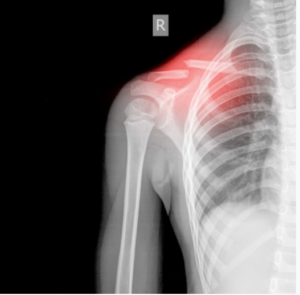

Clavícula

Una caída con traumatismo directo sobre el hombro es la causa más frecuente de lesión de la clavícula.

En estos pacientes se puede observar una deformidad, crepitación y dolor en el foco de la fractura. El soporte del hombre en cabestrillo o vendaje en “8” durante 4 semanas será el tratamiento de esta fractura.

Ya conociste las fracturas más comunes en los niños. Si alguno de tus hijos tiene algún accidente en el campamento o durante las vacaciones es muy probable que tu médico le ordene hacer Rayos X para verificar si en efecto sufrió una fractura y la magnitud de esta. Si fuese el caso, en El Señorial Centro de Imágenes puedes hacer las placas de tus hijos y conocer el tipo de fractura que tuvo. Nos puedes llamar al (787) 764-9493 para más información.